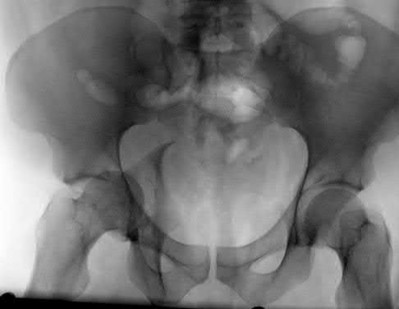

Which of the following images shows an injury pattern most consistent with a lateral compression type 3 pelvic ring injury?

Figure C is an axial CT scan of a lateral compression type 3 (LC3) pelvic ring injury.

Classically, LC3 injuries demonstrate an ipsilateral lateral compression and a contralateral APC (windswept pelvis) fracture pattern. The most common mechanism of injury in these cases is a rollover MVC or pedestrian vs. auto. LC1 injuries are characterized by an oblique or transverse ramus fracture and ipsilateral anterior sacral ala compression fracture, while LC2 injuries consist of a rami fracture and ipsilateral posterior ilium fracture dislocation (crescent fracture). While LC1 injuries can often initially be managed conservatively with protected weight-bearing and close observation, LC2 and LC3 pelvic ring injuries are almost universally operative.

Pennal et al. discuss a radiologic technique for assessing the forces producing pelvic disruption and its use in logically classifying pelvic injury. Based on this radiologic assessment and along with some biomechanical studies, they propose a classification system involving three major forces producing injury that can also be helpful in the management of these patients.

Young et al. performed a retrospective analysis of the plain radiographs of 142 cases of pelvic fractures and identified four patterns of force that presented with distinctive, recognizable radiographic appearances. They describe a classification system for pelvic fractures based on radiographic and clinical findings that correlates with associated injury to soft-tissue structures and enables the surgeon to begin corrective procedures rapidly.

Incorrect Answers:

Answer 1: This represents a lateral compression type 2 injury. Answer 2: This represents a lateral compression type 1 injury.

Answer 4: This represents an anterior posterior compression type 2 injury. Answer 5: This represents an anterior posterior compression type 3 injury.